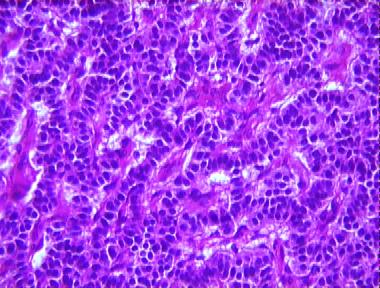

metastatic carcinoid tumor

Histologic Features